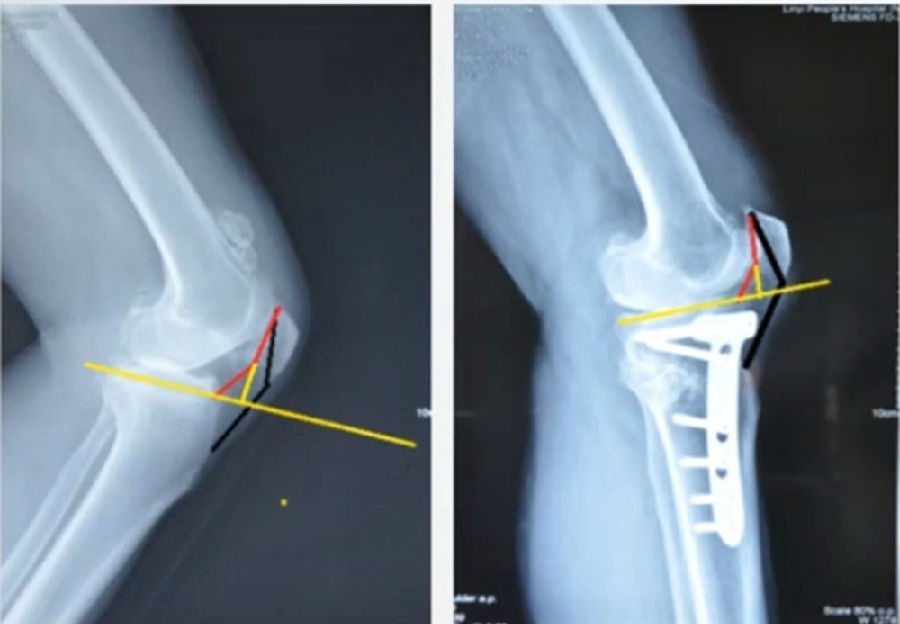

4、OWHTO对髌骨高度影响?

(1)OWHTO可分为上行性或下行性两种截骨方式。

(2)上行性OWHTO可降低髌骨高度的2%-11%;当髌骨高度下降10%,可引起髌股关节压力改变,引发膝前痛。

OWHTO上行截骨与下行截骨

(3)下行性OWHTO对髌骨高度影响较小。

(4)术前存在低位髌骨、髌股关节炎或内翻矫正度数较大时可考虑下行性OWHTO。

有文献证实下行截骨对髌骨的高度确实没有明显影响。

OWHTO下行截骨对髌骨的影响